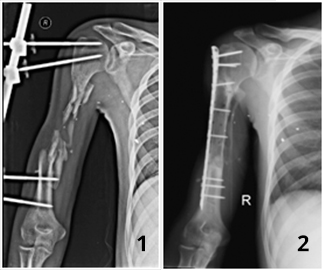

У пациента 26 лет в результате пулевого ранения образовался дефект правой плечевой кости на протяжении до 15 см (см. фото слева). За помощью обратился через 15 мес после ранения. До обращения проходил лечения в других лечебных учреждениях, где какой-либо помощи в восстановлении дефекта кости пациенту оказать не смогли. Нами было проведено реконструктивно-восстановительное оперативное лечение с использованием клеточных технологий. В результате проводимого лечения через 6 мес целостность плечевой кости была восстановлена (см. фото справа) и пациент смог полноценно пользоваться конечностью.